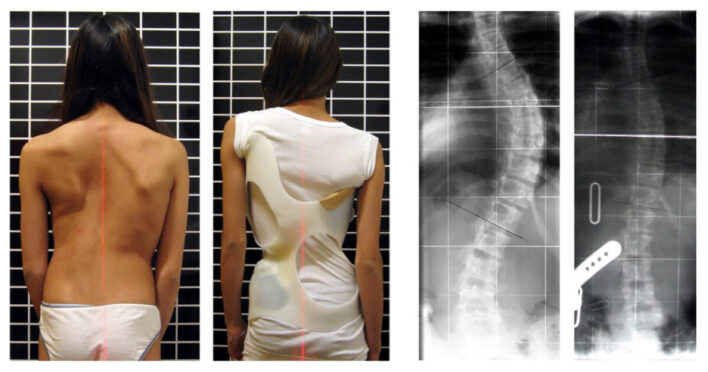

Trường hợp vẹo cột sống 20-400

Mang áo nẹp (cổ) ngực- thắt lưng- cùng:

Nhằm ngăn ngừa vẹo tăng thêm đồng thời có tác dụng nắn chỉnh lâu dài. Tuy nhiên, bệnh nhi thường ít tuân thủ đúng thời gian mang áo nẹp. Nói chung, bệnh nhi thường chỉ đeo khoảng 65% thời gian chỉ định (DiRaimondo, 1988). Thường mang cho đến khi bệnh nhân đạt Risser độ 4 hoặc 5.

Tác dụng của áo nẹp:

- 74% làm ngừng tiến triển đường cong (không mang nẹp 34% ngừng tiến triển).

- Với đường cong 20 º – 29 º chỉ có 40% bệnh nhi mang áo nẹp cuối cùng cần phải phẫu thuật, so với 68% ở những trẻ không mang nẹp.

Một số loại nẹp:

- Nẹp Milwaukee: loại nẹp này bó sát vào người, bao gồm các khung kim loại được gắn với đai chậu bằng nhựa, một vòng cổ bằng kim loại, cùng một cái đỡ cằm, dành cho vẹo cột sống ngực cao.

- Nẹp nhựa Boston: là nẹp (khuôn) nhựa giống một áo jacket ôm lấy thân từ hố nách xuống hông và bệnh nhân vẫn có thể mặc áo bình thường bên ngoài. Áp dụng cho những trường hợp vẹo cột sống ngực – thắt lưng dưới T8.

- Nẹp Cheneau, Wilmington, Kalibis …